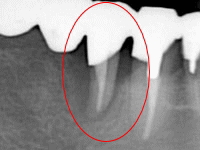

歯周組織の状態を調べるために、歯周ポケットの深さを計ったり、レントゲンを撮ったり、その他治療に必要な検査を行います。エムドゲインゲルを使った治療が行えるかどうがは、歯周病の程度や患者さんの健康状態によっても異なります。

手術は麻酔をかけますので、痛みはありません。まず最初に治療する部分の歯肉を切開し剥離します。歯根の表面の清掃を行いエムドゲインゲルを塗布します。最初に切開した歯肉部分を縫合し、終了です手術後はゆっくりご自宅で休んで頂き、後日感染を防ぐため消毒します。安定したら抜糸します。